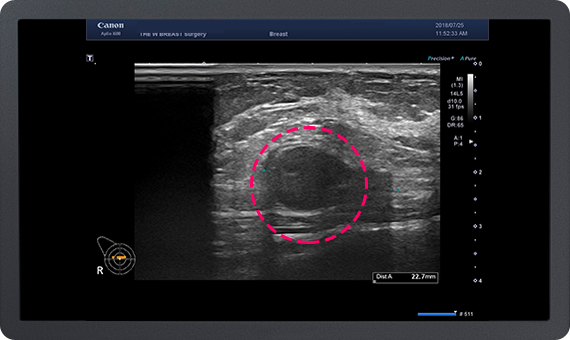

가슴지방 이식 수술 후 발생하는 가장 많은 부작용은

지방 낭종과 석회화입니다.

이에 대해 많은 경험을 가진 THE W 유방센터에서는

지방 이식 후 발생한 지방낭종과 석회화의 제거가 가능하며,

지속적인 유방암 추적이 가능합니다.